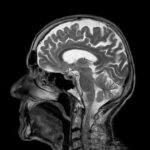

What Should I Know About MRI? by wpengine | Jul 8, 2018 | Home Page Posts | 0 comments If your doctor recommends an MRI, it’s important to understand both the value of the procedure to your health care plan and the risks it may pose. Below are the basics you should know about MRI before you come to your imaging appointment.